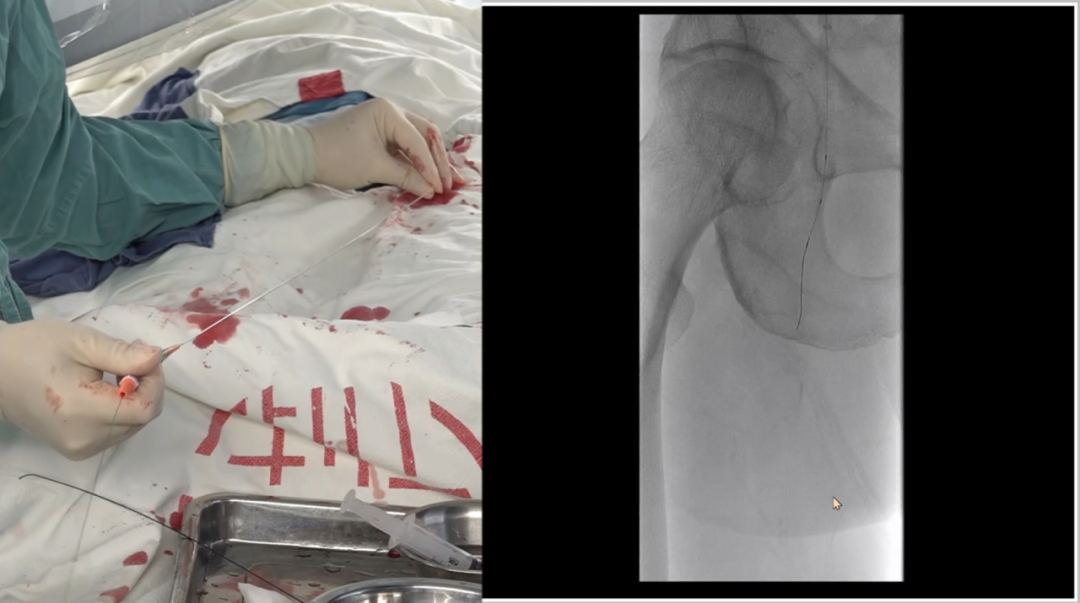

导丝突破:多种器械配合,应对坚硬病变

初始使用单弯导管配合Command18导丝尝试突破股动脉起始段纤维帽,未成功;

更换Terumo导丝后突破纤维帽,但支撑导管跟进困难,提示病变质地坚硬;

先后尝试Command 18、Treasure12 CTO导丝等,均难以顺利通过病变段;

关键技巧:采用"自制CTO导丝"——剪除V18导丝部分软头,塑形后利用其强支撑性,顺利通过病变并跟进支撑导管。